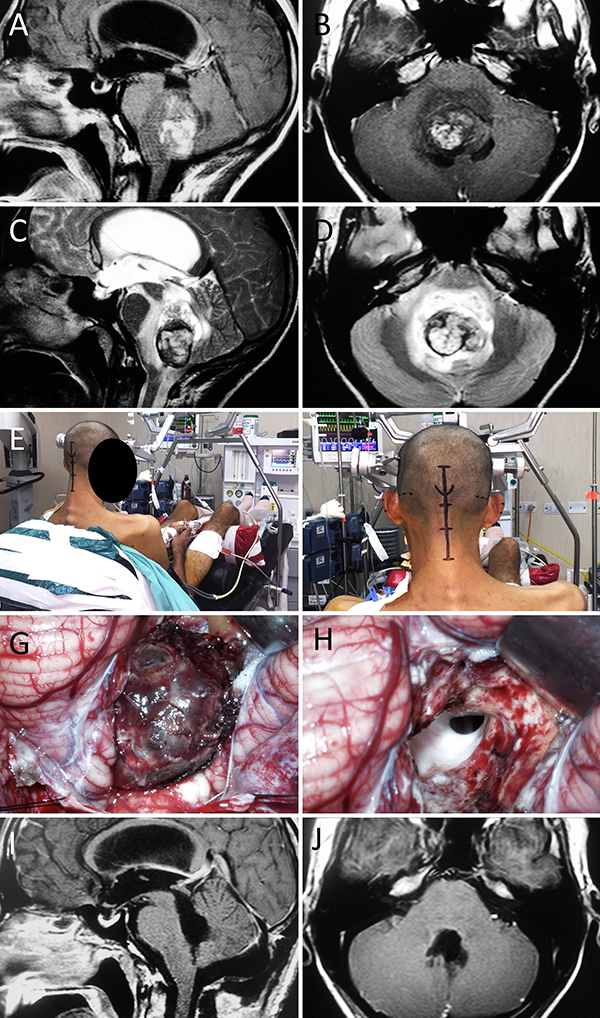

Figura 2: Malformación de Chiari tipo I con siringomielia. A-B: RM preoperatoria; C-D: Posición; E-F: Hallazgos intraoperatorios; G-H: RM postoperatoria.

Figura 5: Méduloblastoma de IV ventrículo. A-D: RM preoperatoria; E-F: Posición; G-H: Hallazgos intraoperatorios. I-J: RM postoperatoria.